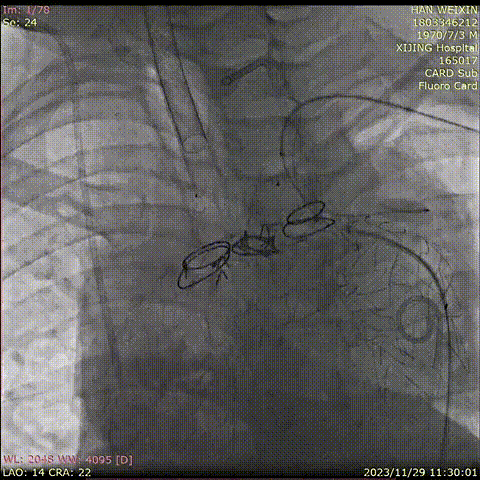

主体支架释放后造影

主体支架窗口

与分支动脉开口存在偏差

利用自适应性成功超选左颈总动脉,并置入分支支架

利用自适应性成功超选无名动脉,并置入分支支架

利用自适应性成功超选左锁骨下动脉,

并置入分支支架

术后造影

术后CTA